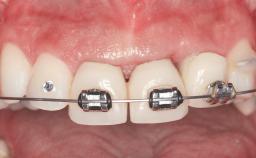

This 20-year-old woman was referred to our department in July 2006. Four months earlier, she had experienced dental trauma to the anterior maxilla when traveling in South America. The emergency treatment included emergency root canal treatment of teeth 12 and 11. Tooth 21 was also subjected to endodontic treatment later. At the initial examination, the patient was not in pain but reported increased mobility of tooth 12. The clinical examination revealed a high smile line, medium thickness of the soft tissue, and rectangular tooth forms. Discoloration of tooth 12 was evident. The periapical radiograph provided by the referring dentist indicated a fracture line at both teeth 12 and 11. A cone-beam computed tomography (CBCT) scan confirmed these fractures. No pathology was found to be associated with tooth 21.